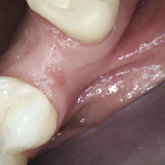

He received his Diploma in Implantology in 2016 from the University of Pretoria, which he passed with Distinction. He is also a member of the International Team for Implantology (ITI), which is based in Switzerland and offers members access to the latest research and cutting-edge techniques.

Porcelain crowns and restorations made in one appointment.

We make it a priority to incorporate the latest in dental technology in everything we do at our practice. ...